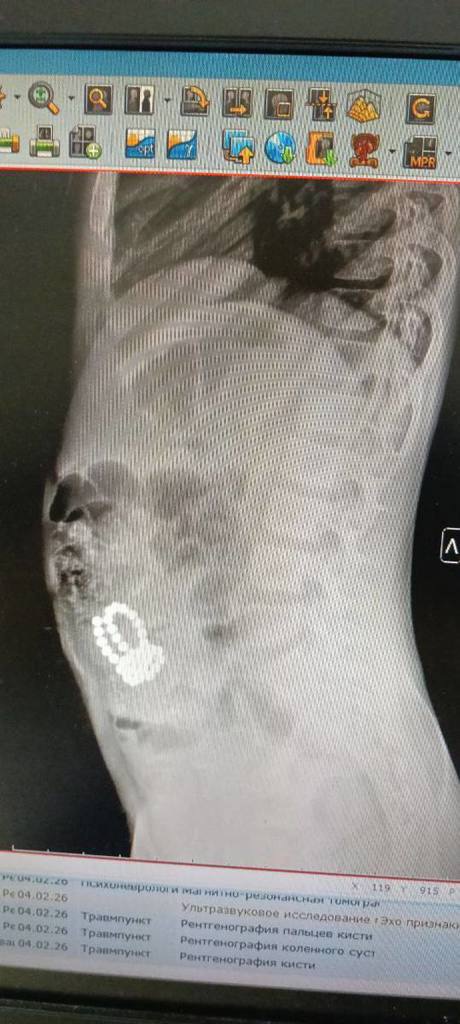

«По линии скорой медицинской помощи в приемное отделение доставили восьмилетнего мальчика с жалобами на боли в области живота и многократную рвоту. После проведения всех диагностических мероприятий, врачи обнаружили множетсво инородных тел в организме. Пациенту экстренно проведена операция — диагностическая лапароскопия, лапаротомия, ушивание перфораций тонкой кишки, удалено 44 магнитных шарика», - рассказывает заведующий детским хирургическим отделением Республиканской детской клинической больницы Минздрава Чувашии Михаил Порфирьев.

Через некоторое время родители доставили в больницу четырехлетнего брата мальчика для проведения обследования подозревая, что младший ребенок тоже мог проглотить магнитные шарики. К сожалению, их опасения подтвердились. В брюшной полости обнаружили 10 магнитиков. Юному пациенту также была проведена экстренная операция — лапаротомия, ушивания перфораций тонкой кишки, удаление магнитов. В данном случае братья вовремя получили необходимую медицинскую помощь.